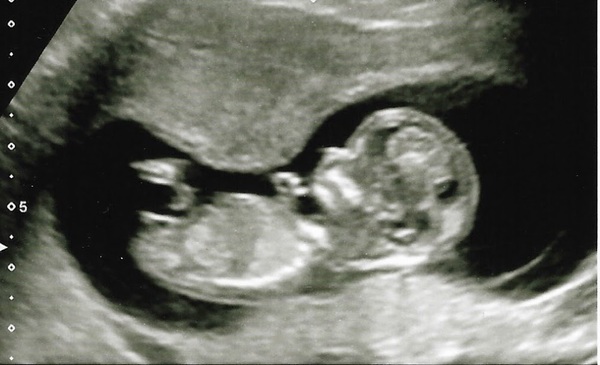

fluffy I think we might get a private gender scan, babybond does them from 16 weeks, I'll be 16+1 on mother's day and thought it would be nice to find out then..I also really want to take my 4 year old to a scan as I think he'll find it fascinating, and can't take him to any of the nhs ones..

So excited about finally getting to 12 weeks (in 1 week from tomorrow!) DH and I were chatting yesterday when we had our belated Valentine's dinner and we're both crazy excited. He's finally talking about cots and pushchairs and names which is great

Still that little niggle in the back of my mind though that there will be something wrong at the 12 week scan despite having two good scans so far. We are definitely going to wait for screening results before telling anyone else though..